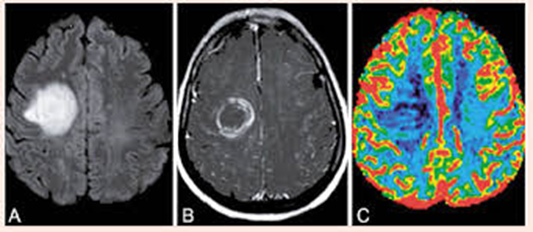

Tumores Cerebrais

Os tumores cerebrais representam um grupo de neoplasias que surgem de diferentes células dentro do sistema nervoso central (SNC) ou de cânceres sistêmicos que metastatizaram para o SNC. Os cânceres sistêmicos